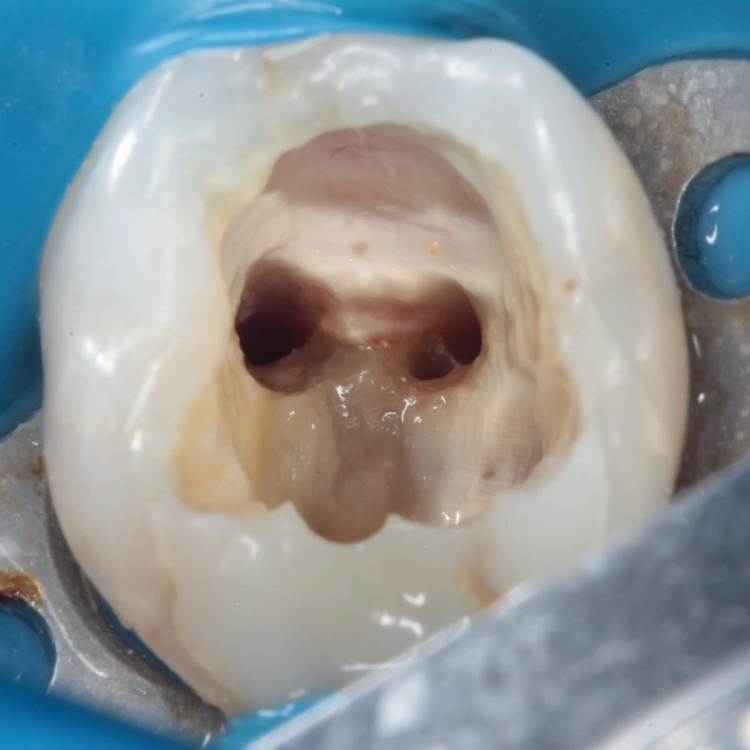

Перфорация закрыта триоксиденом, очень классный материал, и главное – наш!))

Для того чтобы при паковке триокси не провалился в каналы, они закрываются фторопластом